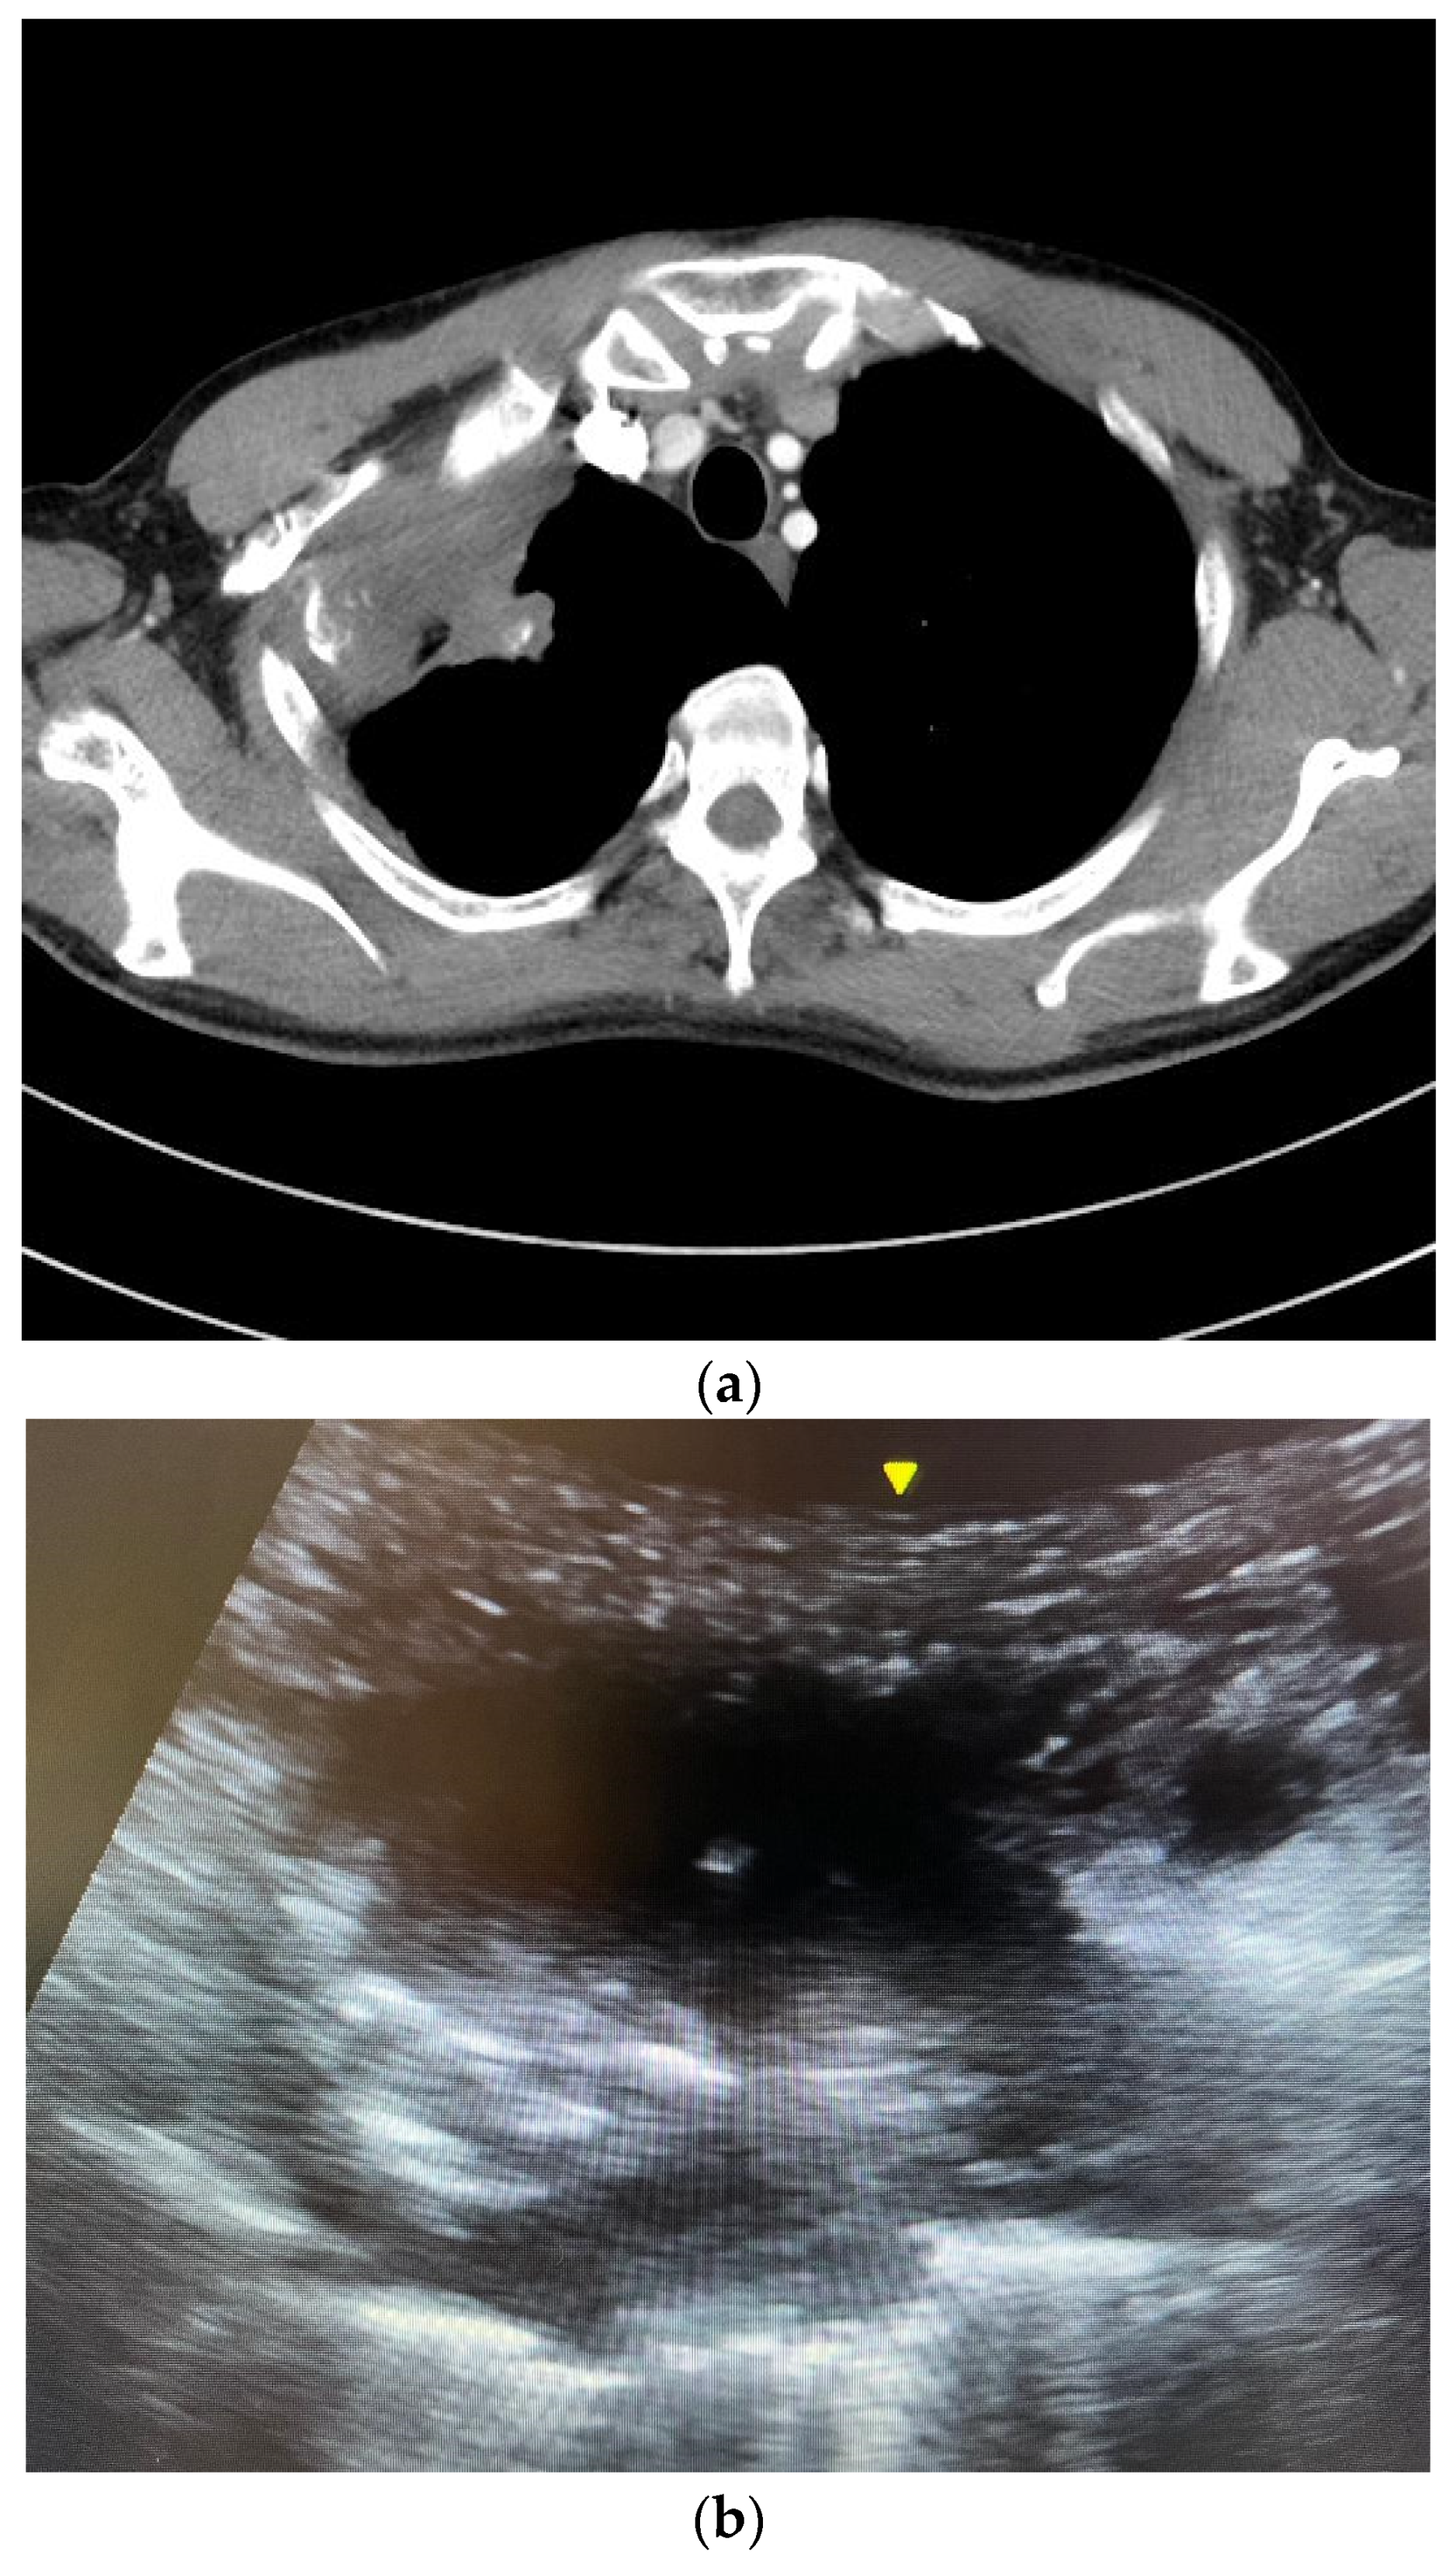

Patients were instructed to sit upright, lie supine or lie lateral. The ultrasound machine Venue 40® or Venue 50® (General Electric, Boston, MA, USA) with curvilinear probe was used to locate the lesion. Color Doppler was employed to check for vessels running through the lesion. The operators would avoid puncturing the vessels during FNA. Under real-time ultrasound guidance and aseptic technique, 5 mL 2% lignocaine was injected percutaneously for local anesthesia. A 22-gauge (22 G) Spinocan® spinal needle (B. Braun, Melsungen, Germany) was inserted, and the needle tip’s position within the target lung lesion was confirmed using a real-time ultrasound exam in the short axis or long axis (Figure 1). The needle stylet was then removed, and a 20 mL syringe was attached to the needle. Four to five in and out motions were made with the needle. At the same time, suction was applied via the 20 mL syringe. Cytological material obtained was injected into a formalin bottle. At least two punctures were made.

Figure 1. (a) A computed tomography image showing a right upper lobe Pancoast tumor. The tumor closely abutted the chest wall, allowing ultrasound-guided percutaneous biopsy. The pathology was squamous cell carcinoma. (b) An ultrasound image of the Pancoast tumor. The tumor had soft tissue density with heterogeneous echogenicity. (c) The yellow circle indicated the position of the needle tip inside the tumor. Several in and out motions were made with the needle, and the needle tip’s position was traced inside the tumor under real-time ultrasound guidance.